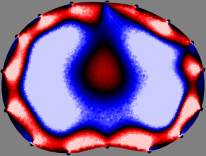

Refer to caption

Figure 2: Fidelity-embedded regularization method. (Left bottom) Correlations between four different column vectors (𝐒ksubscript𝐒𝑘{\bf S}_{k}) and all the remaining column vectors (𝐒subscript𝐒{\bf S}_{\ell}) are visualized. (Right bottom) Performances of the proposed fidelity-embedded regularization method for λ=𝜆\lambda=\infty are shown by numerical simulations.

To explain the FER method, we closely examine the correlations among column vectors of the sensitivity matrix 𝕊𝕊\mathbb{S}, described in Fig. 2. The correlation between 𝐒ksubscript𝐒𝑘{\bf S}_{k} and 𝐒subscript𝐒{\bf S}_{\ell} can be expressed as

for i=1,,16𝑖116i=1,\cdots,16[23]. This shows that the column vector 𝐒ksubscript𝐒𝑘{\bf S}_{k} is like an EEG (electroencephalography) data induced by dipole sources with directions uj,j=1,,16formulae-sequencesubscript𝑢𝑗𝑗116\nabla u_{j},j=1,\cdots,16 at locations ΔksubscriptΔ𝑘\Delta_{k}. Given that two dipole sources at distant locations produce mutually independent data, the correlation between 𝐒ksubscript𝐒𝑘\mathbf{S}_{k} and 𝐒subscript𝐒\mathbf{S}_{\ell} decreases with the distance between ΔksubscriptΔ𝑘\Delta_{k} and ΔsubscriptΔ\Delta_{\ell}. Fig. 2 shows a few images of the correlation 𝐒k,𝐒(|𝐒k||𝐒|)1subscript𝐒𝑘subscript𝐒superscriptsubscript𝐒𝑘subscript𝐒1\left\langle\mathbf{S}_{k},\mathbf{S}_{\ell}\right\rangle(|\mathbf{S}_{k}||\mathbf{S}_{\ell}|)^{-1} as a function of \ell for four different positions ΔksubscriptΔ𝑘\Delta_{k}. The correlation decreases rapidly as the distance increases. In the green regions where the correlation is almost zero, 𝐒subscript𝐒{\bf S}_{\ell} is nearly orthogonal to 𝐒ksubscript𝐒𝑘{\bf S}_{k}.